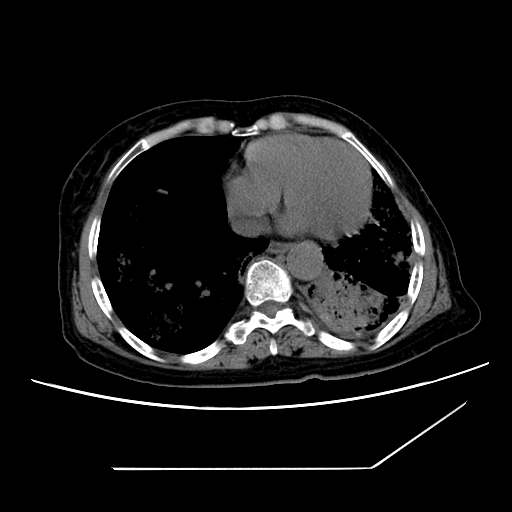

标题: CT25393:病人45岁,咳嗽,吐黄痰带血丝,发热,胸闷月余 [打印本页]

标题: CT25393:病人45岁,咳嗽,吐黄痰带血丝,发热,胸闷月余

1、左肺中央型肺癌并双肺弥漫性转移   2、双肺部感染    3、肺大泡     4、左侧胸腔积液

双侧肺弥漫性病变,可见“空泡征”及“蜂窝征”,考虑肺泡癌可能性大,左侧胸腔积液,考虑胸膜受累可能!

考虑肺泡癌,建议排除感染。

考虑肺泡癌

1)不排除肺泡癌可能。2)左侧胸腔积液。